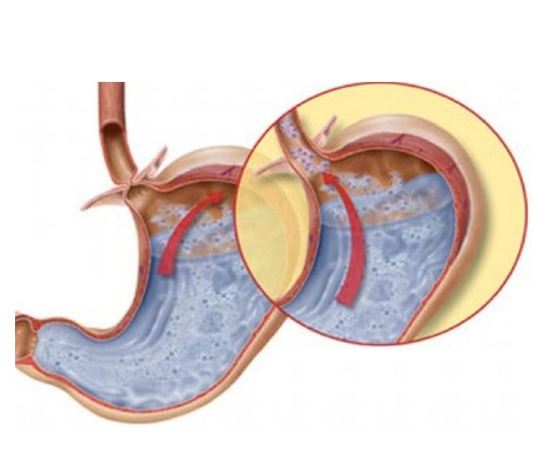

Reflujo gastroesofágico.

medinova.gr

Este mal consiste en la disfunción del músculo final del esófago, el cual no puede cerrarse bien, por lo que hace que el contenido del estómago suba. Esta situación provoca eructos excesivos y requiere tratamiento médico.